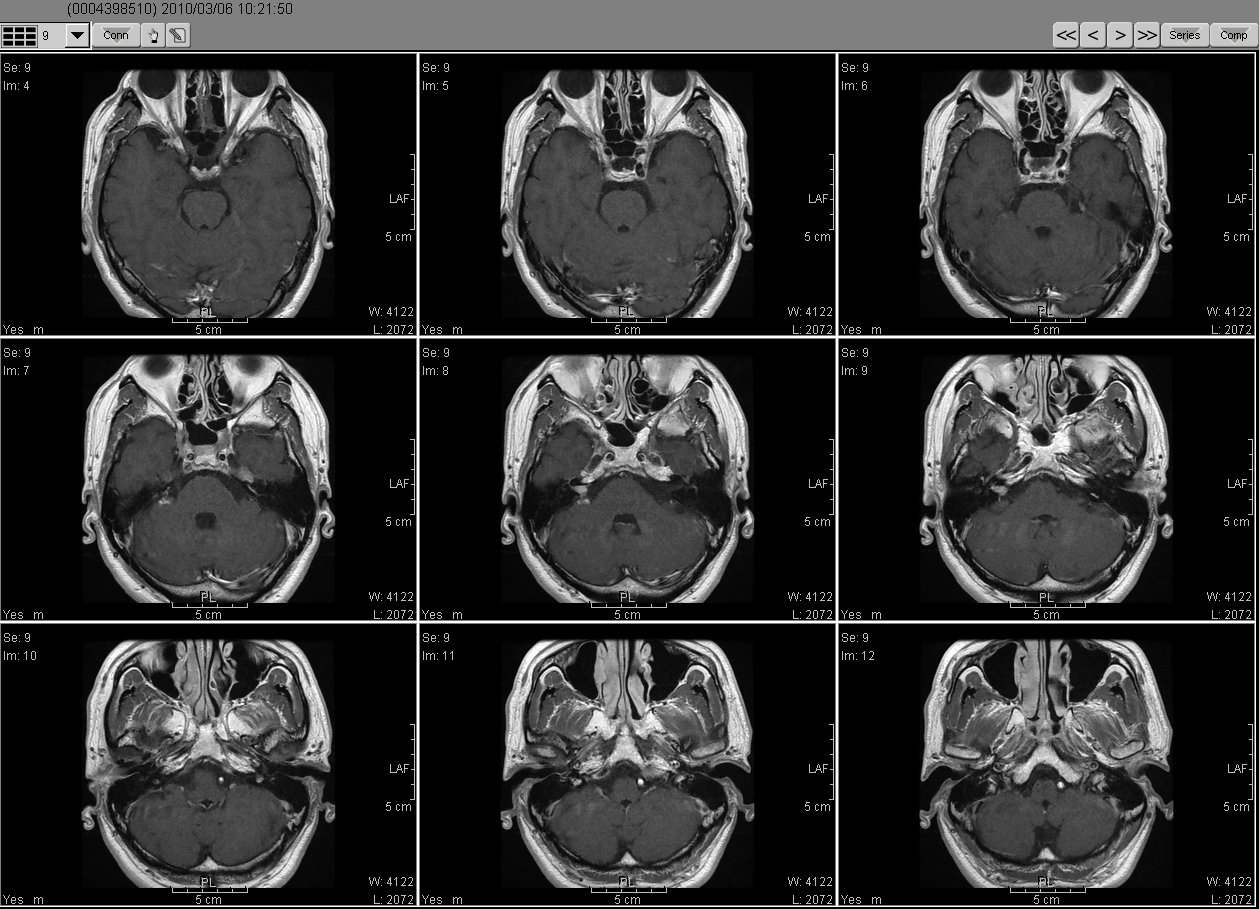

2010_03_06 MRI

2010_03_06MRI01